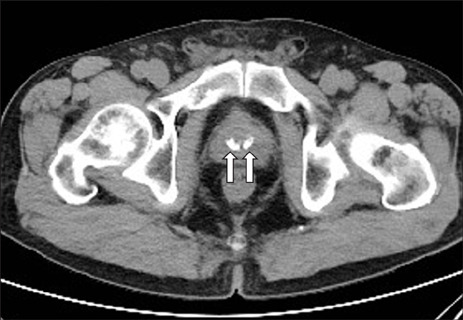

전립선 크기를 측정하기 위해서 경직장 (전립선) 초음파를 시행하다 보면 종종 전립선내 결석을 관찰하게 된다. 또한 요로 결석을 확인하기 위해서 복부 CT를 촬영했을 적에도 우연히 전립선내 결석을 확인하는 경우가 있다. 문제는 이런 전립선내 결석이 생각보다 흔히 보게 된다는 점이다.

wjmh-36-15-g005-l.jpg 복부 CT에서 전립선내 결석(화살표시)

전립선내 결석은 대개 큰 문제를 일으키지 않지만, 혈뇨나 요정체같은 배뇨 문제나 회음부 및 골반통증과 같은 증상들과 연관된다.